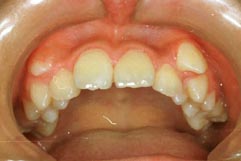

1.叢生(乱ぐい歯) 歯が重なり合ってでこぼこしています

治療後